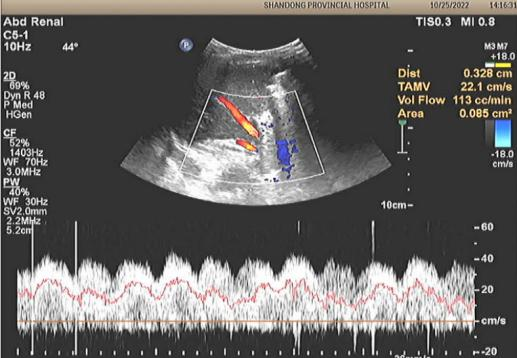

术后血管超声

10月20日,在麻醉手术科满敏主任医师、刘希江副主任医师配合下,在小儿普外科刘桂海主任医师指导、焦晨炜副主任医师配合下,王刚主任医师主刀手术,为患儿做了腹腔镜下门体静脉分流结扎术,顺利在异常分流静脉的起始部左侧做了精准结扎。术后,复查血管超声示门体静脉分流已得到纠正,肝血流恢复。在小儿重症医学科和小儿普外科的精心治疗下,患儿各项异常指标迅速恢复正常,顺利出院。